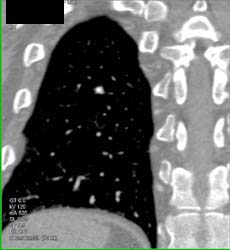

Pulmonary Embolism